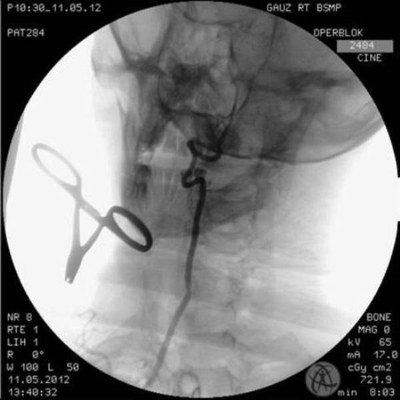

37-летний мужчина, поступивший в БСМП с тяжелым компрессионным переломом шейного отдела позвоночника, родился в рубашке. Во время операции произошла внештатная ситуация - кровь хлынула из позвоночной артерии, которая "питает" заднюю часть головного мозга. "Поврежденные стенки артерии нельзя было зашить - они находятся в костном канале, - рассказывает заведующий отделением рентгенангиохирургии Булат Загидуллин. - Было принято решение закрыть дефект внутрисосудисто, изнутри. Вряд ли нам удалось это сделать без последствий, если бы не использовали ангеограф, аппарат, позволяющий увидеть состояние сосуда во время операции". Пациент под наблюдением медиков был две недели, вчера его выписали домой.